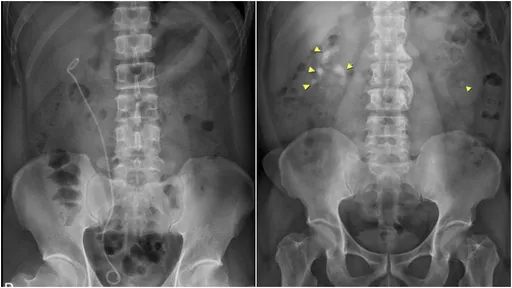

...腸直腸癌或子宮頸癌治療術後,或子宮內膜異位等,造成輸尿管狹窄或封閉,往往需要長期的雙J導管置換來改善...

...蹤,若影響腎功能,則須考慮手術,例如體外震波碎石、輸尿管鏡取石,或放置雙J管幫助引流。當腎臟因反覆感...

...的情況,則可能需要手術,常見手術方式包括硬式與軟式輸尿管鏡,後者能處理腎臟及整段輸尿管的結石,安全性...